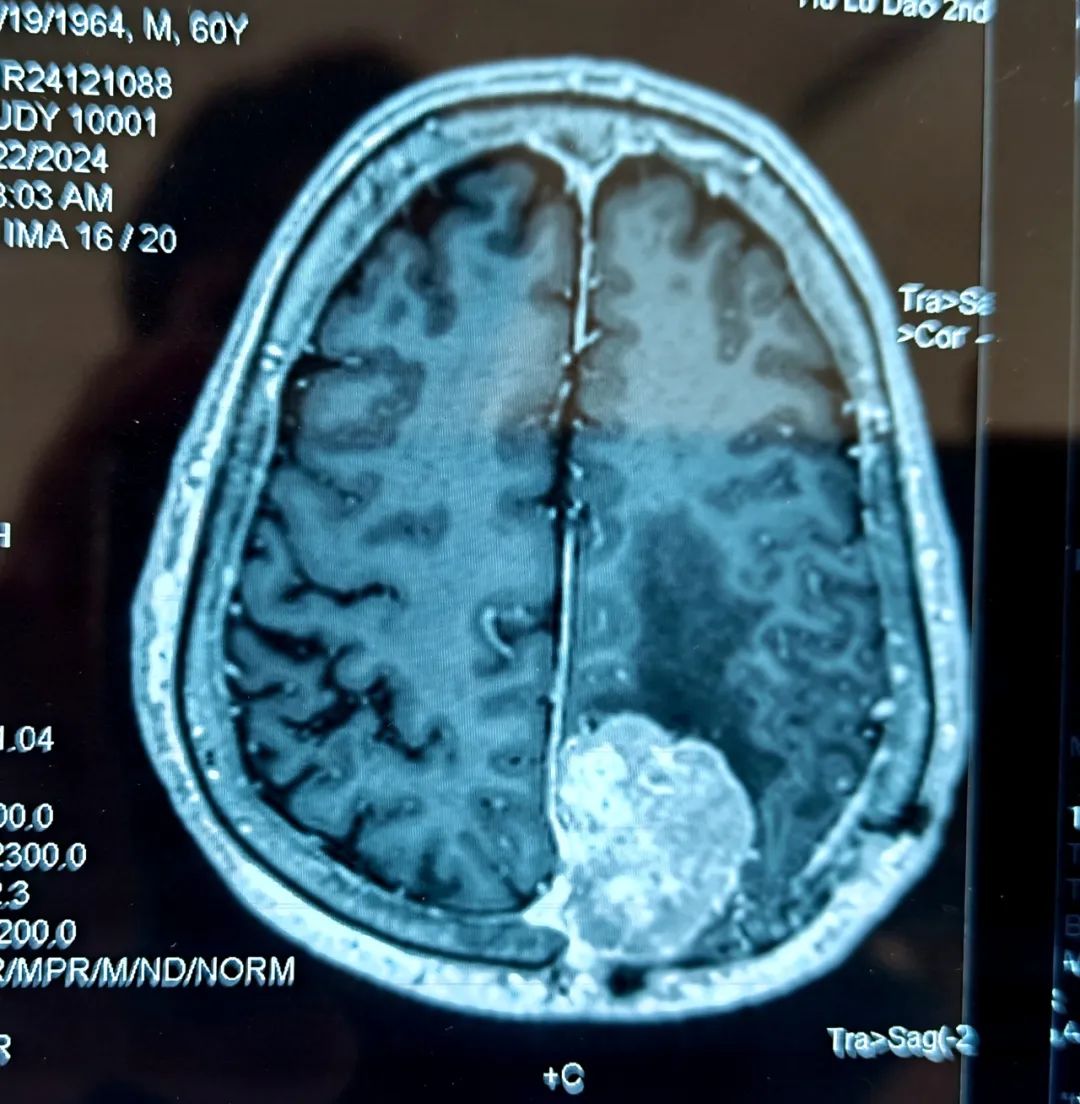

患者为60岁男性,十年前在北京某医院行右顶部矢状窦旁脑膜瘤切除术,因肿瘤侵蚀颅骨,当时切除肿瘤后同时给予部分颅骨切除一期颅骨修补术,病理诊断为非典型脑膜瘤,术后未行放疗,也未定期复查CT及MRI。三个半月前,患者因脑梗塞住院,检查时却意外发现脑膜瘤复发,且肿瘤最大直径已达5.2cm,属于巨大脑膜瘤。

- 患者术前核磁 -

情况紧急,神经内科立即邀请神经外科桑文渊主任会诊。桑主任经过询问患者病史、查体、阅片后,明确复发脑膜瘤的诊断,并与患者家属仔细沟通,表明肿瘤体积巨大且患者有头痛症状,需要待脑梗塞病情稳定后再次行手术切除肿瘤。经过耐心的病情剖析,家属对于手术的必要性表示理解。